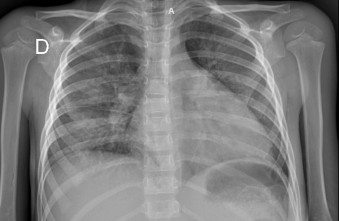

The patient began to have increased diuresis with progressive negative water-electrolyte balances. With the new treatment, the abdominal perimeter was reduced to 64 cm; in addition, there was a decrease in scrotal edema and disappearance of edema in his lower limbs. Likewise, there was an improvement in the liver profile (GOT 265, GPT 66 and albumin 3.61) and the coagulation profile (PT 14.5" 87 %, APTT 33.9", INR 1.09 and fibrinogen 177). On the twentieth day of hospitalization, the patient was afebrile, the scrotal edema had disappeared, and his abdominal perimeter was 58 cm. He had no jaundice on his skin and only mild jaundice in his sclerae; furthermore, there was there was improvement in the liver profile (TB 2.39, DB 1.82, GOT 81 and GPT 35) and the coagulation profile (PT 13.9, APTT 32.9, INR 1.04 and fibrinogen 274). In addition, the following results were obtained: LDH 1,087, ferritin 2,000 and CRP 1.53. He received antibiotic therapy for 14 days, albumin for nine days, and furosemide as a continuous dose for three days, followed by bolus dosage after the administration of albumin. The next day, he presented with respiratory difficulty; thus, a chest X-ray was taken, revealing cardiomegaly and pulmonary congestion. The cardiologist diagnosed congestive heart failure due to dilated cardiomyopathy.

The echocardiogram evidenced left ventricular systolic dysfunction, with a left ventricular ejection fraction (LVEF) of 39 %, D-dimer 6.98 ug/mL, ferritin 522 ng/mL, TB 1.72, GOT 49, GPT 30, creatinine (Cr) 0.47 and CPK MB 12.20. Therefore, the prescribed treatment was captopril 6.25 mg po every 12 hours and carvedilol 3.125 mg po every 12 hours, and he continued his treatment with diuretics. Finally, he was discharged afebrile, without edema and with resolution of liver failure and coagulation disorder (Figures 2 and Figure 3).

Figure 2 Chest X-ray showing severe cardiomegaly and pulmonary congestion